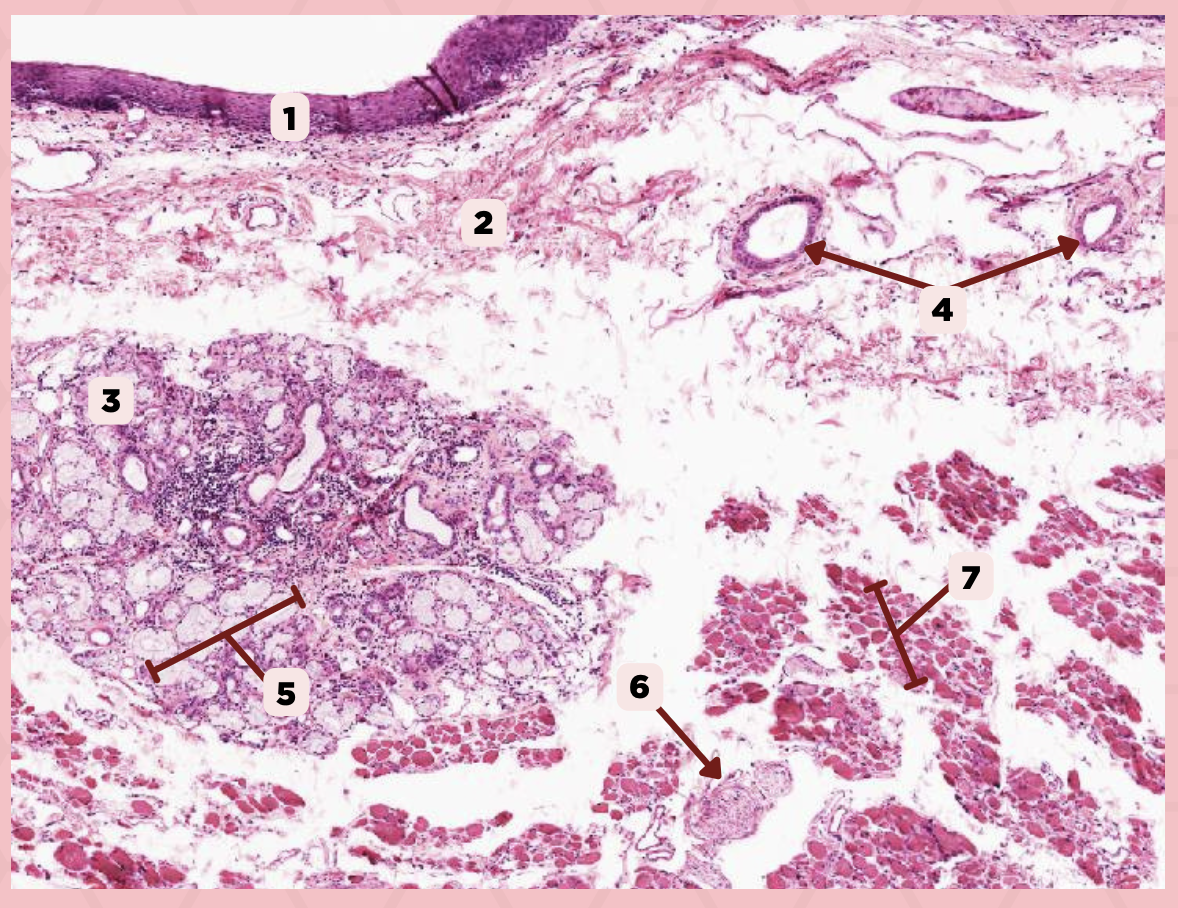

Lip

What is the specimen showed in the picture?

Epidermis

Identify the structure labeled as 1.

Dermis

Identify the structure labeled as 2.

Arrector Pilli Muscle

Identify the structure labeled as 3.

Hair Follicle

Identify the structure labeled as 4.

Sebaceous Glands

Identify the structure labeled as 5.

Lip

What specimen is showed in the picture?

Labial Glands (in the Mucosa)

Identify the structure labeled as 1.

Skeletal Muscle Cells

Identify the structure labeled as 2.

Lamina Propria

Identify the structure labeled as 3.

Mucosa

Identify the structure labeled as 4.

Lip

What specimen is showed in the picture?

Skeletal Muscle Fibers

Identify the structure labeled as 1.

Labial Glands

Identify the structure labeled as 2.

Cheek

Identify the specimen.

Mucosa

Identify the structure labeled as 1.

Lamina Propria

Identify the structure labeled as 2.

MALT

Identify the structure labeled as 3.

Blood Vessels

Identify the structure labeled as 4.

Buccal Glands

Identify the structure labeled as 5.

Nerve

Identify the structure labeled as 6.

Muscle Fascicles

Identify the structure labeled as 7.